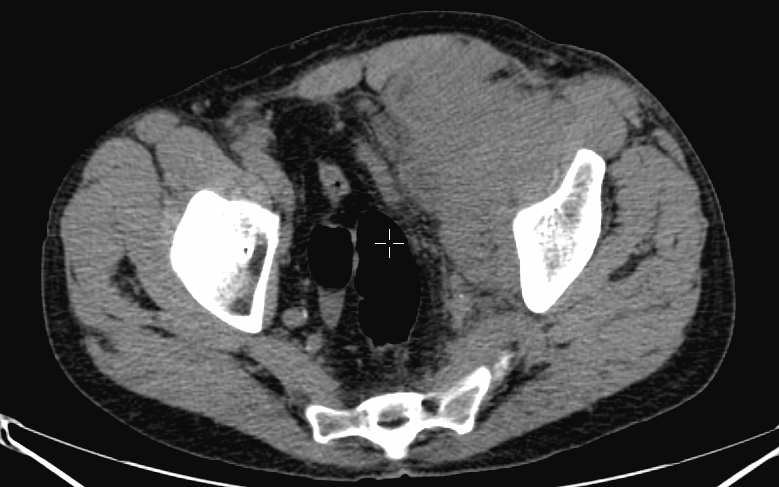

The most important and most commonly used isotope examination of the musculoskeletal system is bone scintigraphy. During the examination the natural component of bone- pyrophosphate analogues, technetium labeled diphosphonate radiopharmaceuticals are used. Following intravenous injection, the radiotracer binds to the hydroxyapatite crystals of the bone. Its uptake in the bones is influenced by blood supply and osteoblast activity. The unnecessary, unbound radiotracers are excreted through the kidneys after about 2-3 hours, scintigraphy is performed during this late metabolic phase. This method consistently depicts bone structure and areas where increased or decreased metabolic activity persist. Usually, whole-body planar images are obtained from an anterior and a posterior direction and additional, optional lateral and oblique measurements can also be performed of targeted lesions if necessary. (Figure 3.)

3. Whole body bone scintigraphy, anterior (a) and posterior (b) acquisitions. Normal findings.

More complex anatomic structures (spine, the base of the skull, facial and hip bones) can be imaged more confidently with SPECT scans. On one hand, they provide a more accurate spatial localization and on the other, with their superior contrast resolution, they are able to differentiate lesions even if planar exams are negative or uncertain. SPECT-CT can characterize the CT morphology of the lesions with pathologic uptake. Thus, it is capable to provide a definitive diagnosis. (Figure 4.)

Image

a

b

c

d

e

4. Bone scintigraphy, prostate cancer. The image set shows the characterization of multiplex increased activity uptake. Posterior whole body scan (a). SPECT-CT coronal fusion images (b,d), CT examination (c,e). Sclerotic lesions in the pelvic bones are suggestive of osteoplastic metastases (b,c), small joint arthrosis at LIII-IV segments, more expressed on the left side (b,c), spondylosis on the right side at LIV-V segments (d,e). (The increased activity spot on the whole body scan, at the left cubital region, is correspondent to the paravasation of the iv. radiopharmaceutical.)